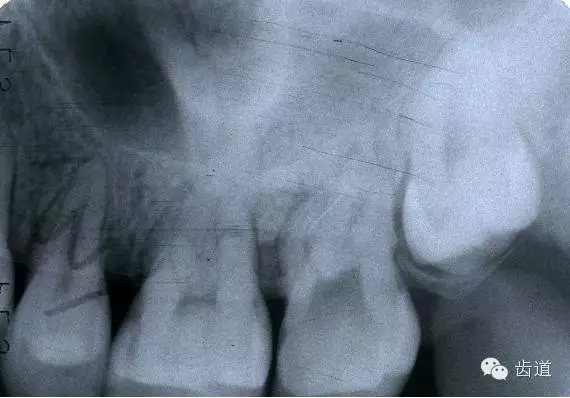

器械折斷在根管內(nèi),阻塞根管,妨礙治療操作。如不能取出,使根管治療不能繼續(xù)進(jìn)行,不得不輔以根尖手術(shù)。

左上7近中頰根器械折斷

右上6腭根器械折斷

折斷于根管內(nèi)的器械要盡量取出,若無(wú)法取出經(jīng)常規(guī)充填后,成功率不受明顯影響。

1.折斷器械有一部分露在根管口外,用鑷子或持針器夾取出。

2.器械斷端在根管口內(nèi):用超聲根管銼在該器械旁增隙,通過(guò)超聲震蕩和沖洗,可將折斷器械從根管內(nèi)震動(dòng)沖出。在手術(shù)顯微鏡下直視操作,大大提高了取出的成功率。

3.折斷器械尖端已超出根尖孔:無(wú)癥狀不處理;有疼痛則作根尖手術(shù)取出。

4.折斷器械較長(zhǎng),各種方法均不能取出,可作根管電解消毒,塑化治療或塑化劑處理,根管充填。

若患牙根尖有病變,必要時(shí)作根尖切除+倒充填。